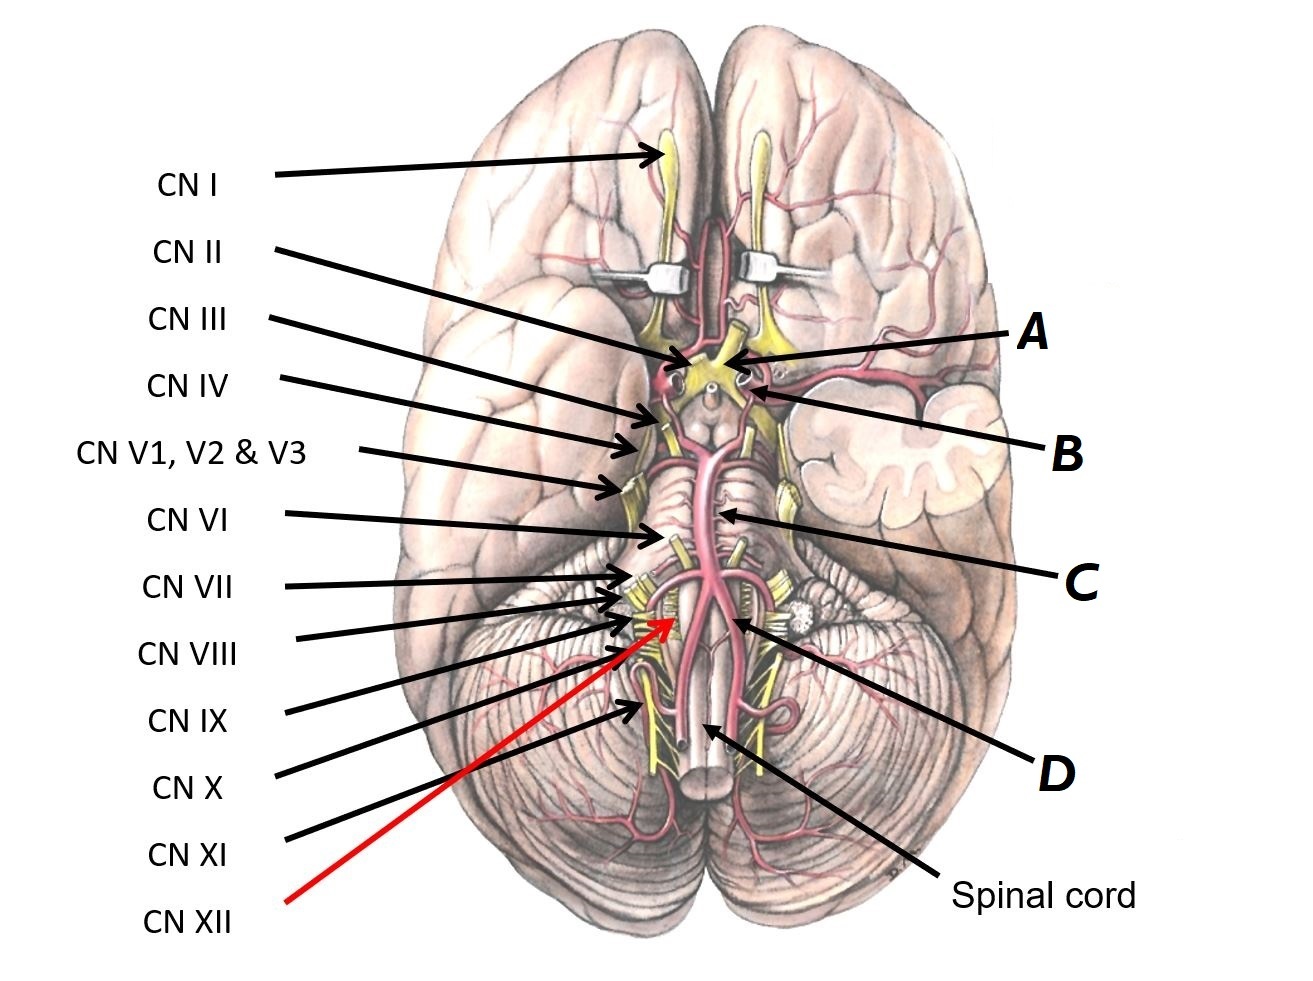

Name nerves A to D

A - CN III (occulomotor nerve)

B - CN IV (trochlear nerve)

C - CN V (trigeminal nerve)

D - CN VI (abducens nerve)

Name structures A, B and C

A - Left internal carotid artery

B - Basilar artery

C - Left vertebral artery